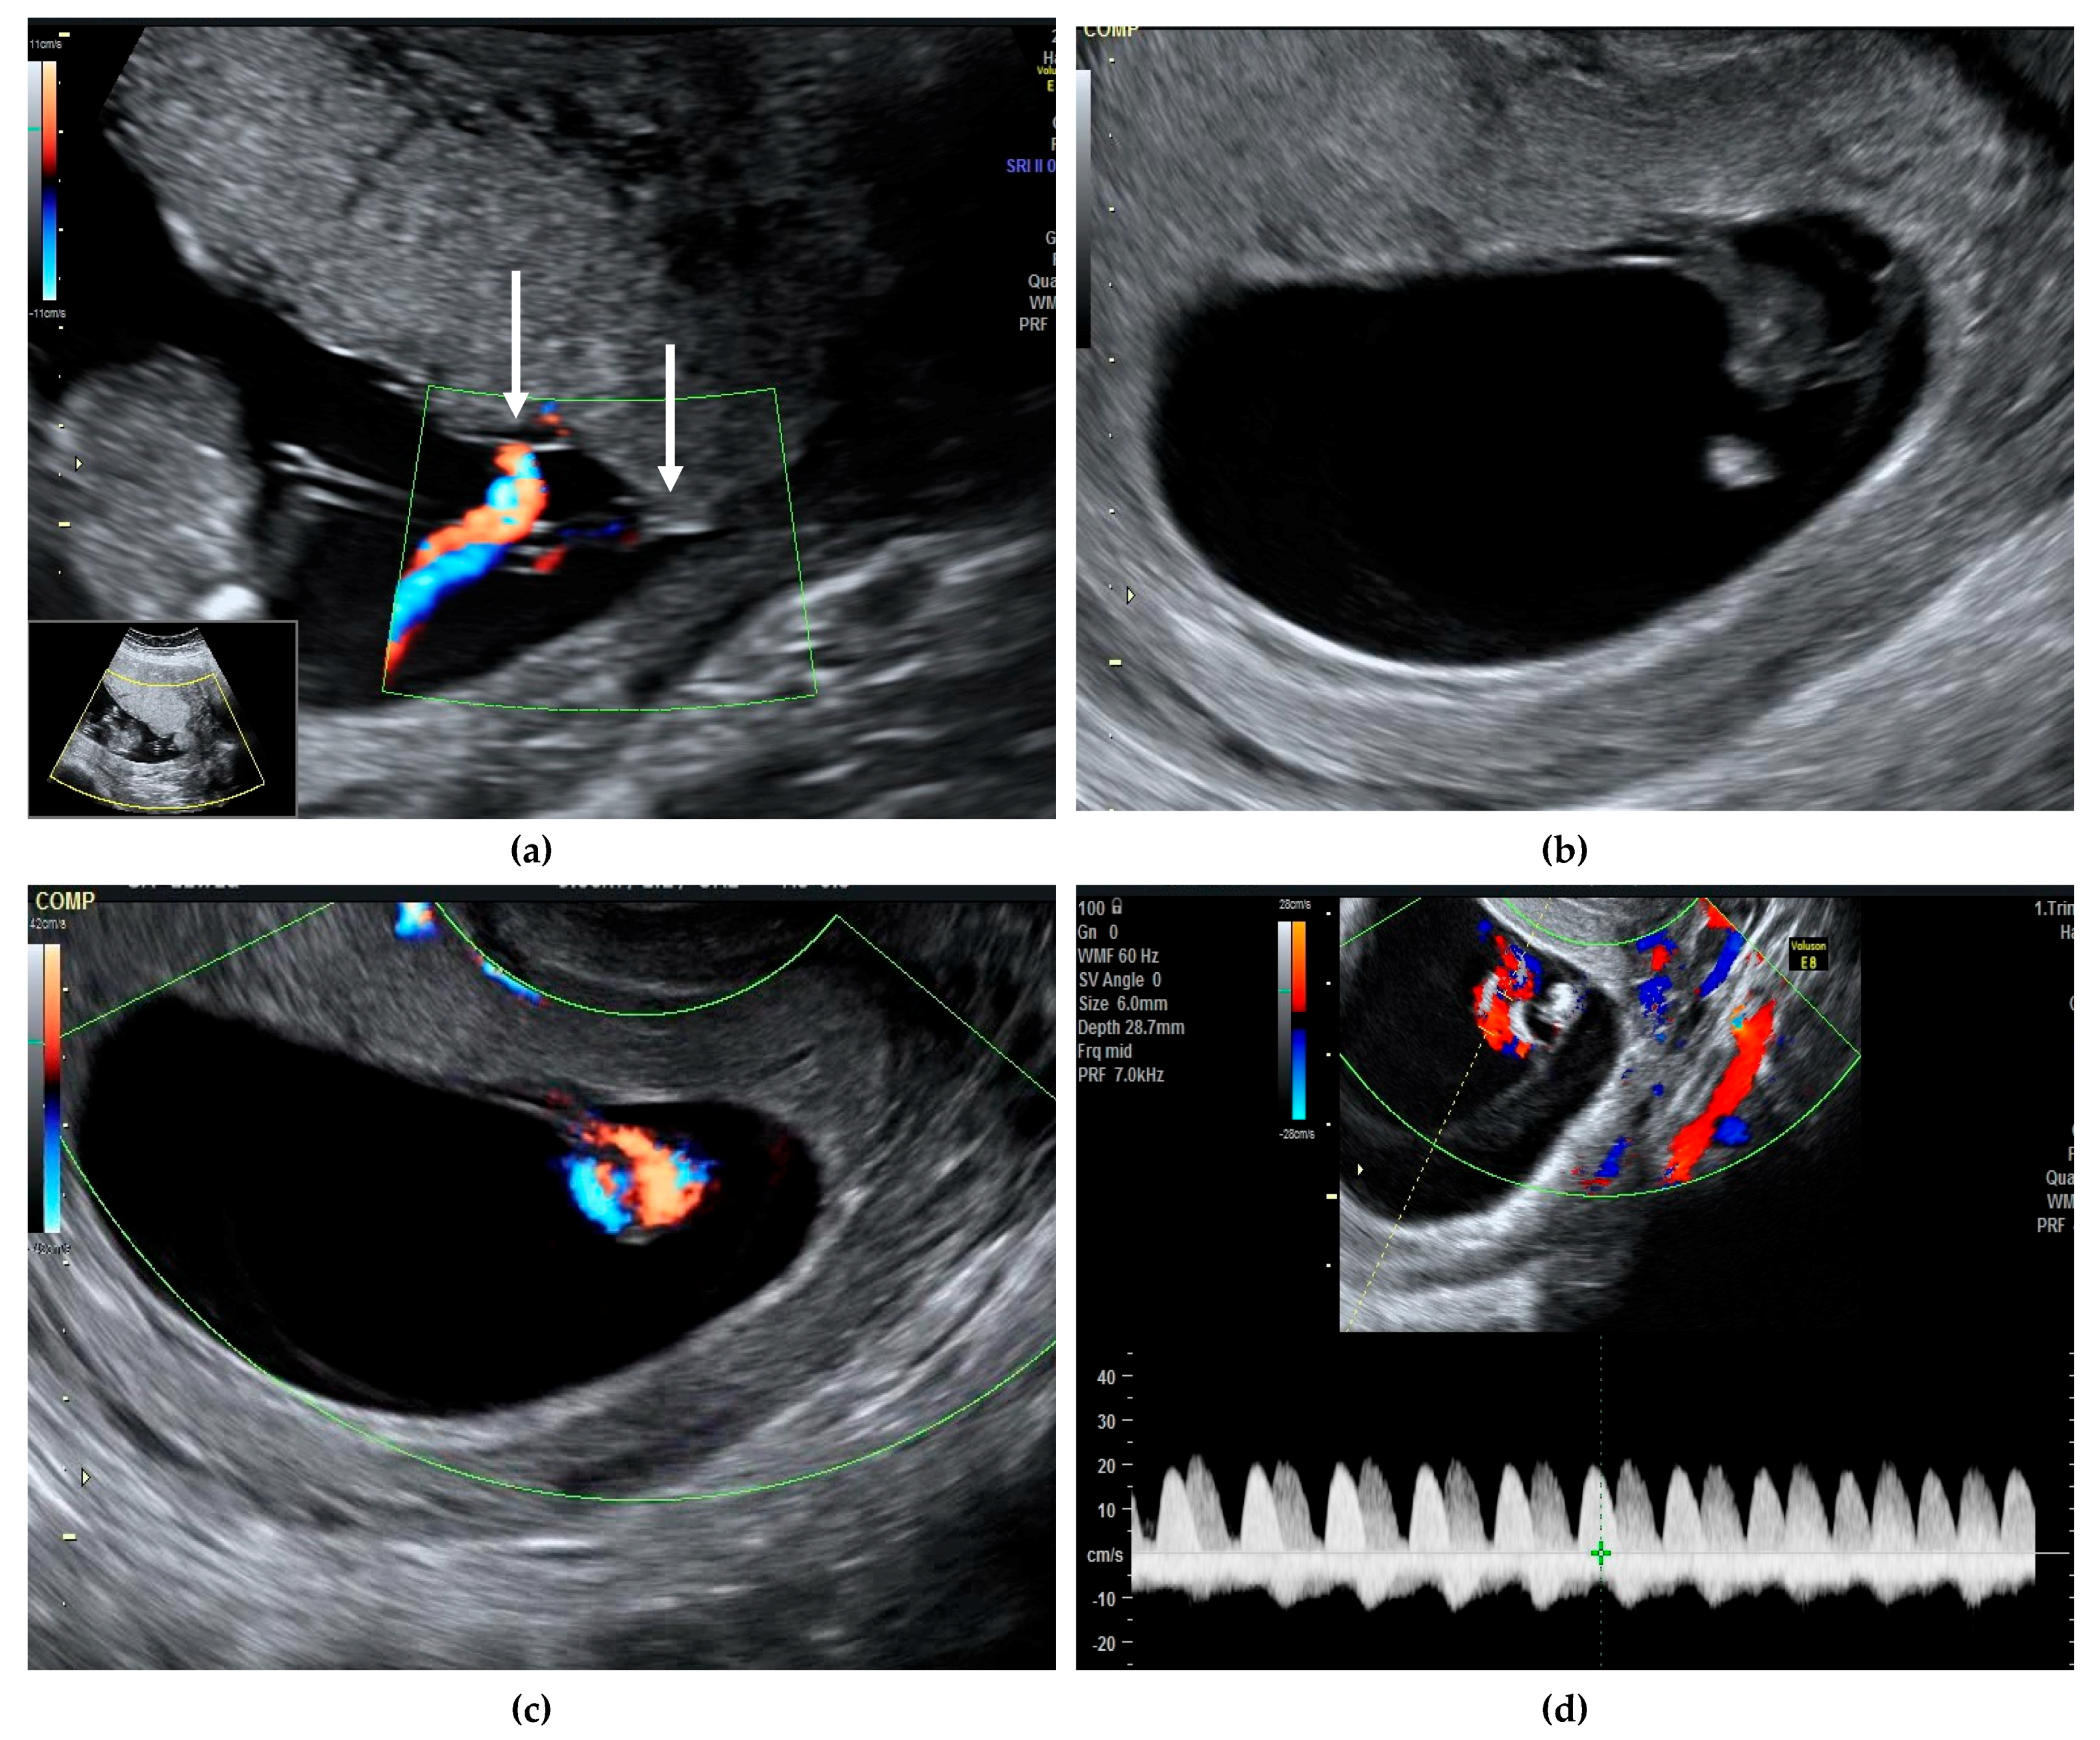

Monochorionic monoamniotic twin pregnancy is rare, with an estimated prevalence of about 1 in 10,000 pregnancies, representing 1–5% of all monochorionic twins [1]. Correct diagnosis and counselling of parents are extremely important, especially regarding the risk of unexpected fetal demise. Without major abnormalities, the rates of fetal loss before 24 weeks are 20% [2] and the risk of perinatal mortality after 24 weeks ranges between 10–20% [2,3]. More recent data reported a lower risk of unexpected fetal death, of about 5–10%, after excluding cases of discordant structural anomalies, spontaneous miscarriage, or complications related to monochorionicity such as twin-to-twin transfusion syndrome (TTTS) [4]. After 32 weeks, the risk of sudden fetal death is 4% and usually involves both twins [5]. Cord entanglement has been evoked as the main cause of sudden death, although other mechanisms such as acute exsanguination through large umbilical anastomoses are likely to be involved, as cord entanglement is present in almost all monoamniotic twins and most of them have a good prognosis after 20 weeks despite this finding [3]. Diagnosis of chorionicity and amnionicity is easily established in the first trimester of pregnancy, along with other major structural defects [6]. Cord entanglement can be identified early in the first trimester using color Doppler and pulsed-wave Doppler by the simultaneous recording of two different heart rates [7] (Figure 1).

Figure 1. We present a case of a 30-year-old G2 P2 with a previous caesarean section, who presented in our unit at 11 weeks gestation for pregnancy confirmation after normal spontaneous conception. A viable monochorionic monoamniotic twin pregnancy was identified, and the common placenta and the cord insertions, very close to one another, were visualized (a, white arrows). The second ultrasound evaluation at 13 weeks did not reveal any structural abnormalities and the risk for aneuploidies was low (Supplementary Materials). Cord entanglement was suspected at this early gestational age, both in gray scale and color Doppler (b,c). Simultaneous registrations of two different heart rates also suggested the cord entanglement (d, represented by white and yellow arrows). The patient was counselled regarding the diagnosis, the possible complications, and the monitoring plan. The follow-up visit was planned for 16 weeks and both Doppler studies and growth were within normal ranges. From 16 weeks onwards, the follow-up scans were booked every second week. Unfortunately, the patient did not attend the 18 weeks scan, but she had a scan at 19 weeks. Sadly, double fetal demise was diagnosed. We acknowledge that this event was unpreventable and that routinely we recommend a scan every second week for reassurance. When fetal death occurs, this is an acute hemodynamic event, therefore previous scans are usually normal.